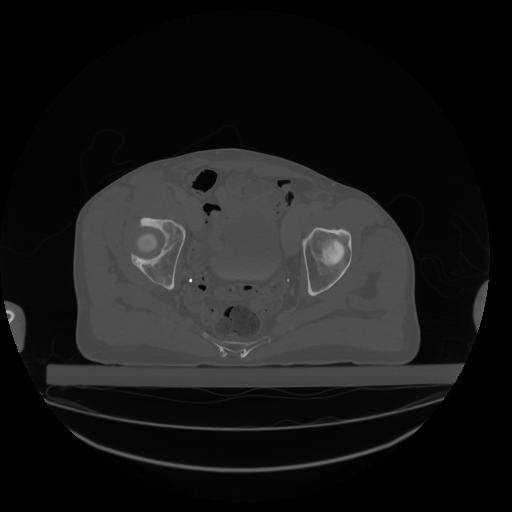

34 CUERPO,CE,Vol,1.0,CUERPO,,